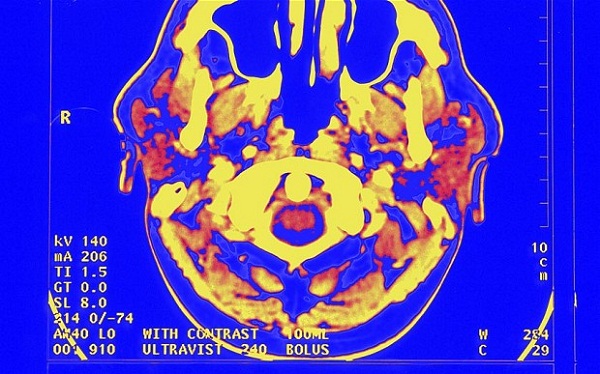

Научници, психолози и англиски академци на универзитетот во Ливерпул откриле дека читањето на делата на класичните писатели има позитивен ефект на мозокот, го задржува вниманието на читателот и поттикнува одразување на сопствениот живот. Со користење на скенери, тие ја набљудувале активноста на мозокот на волонтери додека читале дела од Вилијам Шекспир, Вилијам Вордсворт, Т.С. Елиот и други. Потоа ги „превеле“ текстовите на поедноставен, модерен јазик и повторно ги набљудувале мозоците на читателите додека ги читале зборовите.

Резултатите покажале дека прозата и поезијата која претставувала поголем предизвик предизвикува многу поголема електронска активност во мозокот отколку „средените“ верзии. Научниците можеле да го набљудуваат мозокот како реагирал на секој збор и да забележуваат како се „осветлувал“ кога читателите стигнувале до необични зборови, изненадувачки фрази или тешки структури на реченици.

Ова „осветлување“ на мозокот трае подолго од првата електрична искра и го поттикнува мозокот на понатамошно читање. Истражувањето, исто така, открило дека поезијата ја зголемува активноста на десната хемисфера од мозокот, делот кој е одговорен за автобиографската меморија, што му помага на читателот да се одрази на своите искуства кои имаат некаква врска со она што го прочитале. Академиците изјавиле дека ова значи дека класиците биле многу покорисни од било која книга за самопомош.

Во првиот дел од истражувањето, била набљудувана мозочната активност на 30 волонтери додека читале делови од драми напишани од Шекспир, вклучувајќи ги „Отело“ и „Магбет“, и повторно додека ги читале текстовите парафразирани во поедноставна форма. Додека ги читале едноставните текстови, електричната активност во мозокот била на нормално ниво. Но, кога го читале оригиналниот Шекспир, нивоата на активност „скокнале“ поради неговото користење на зборови кои се непознати за читателите. Следната фаза од истражувањето вклучува барање начин на кој поезијата може да обезбеди терапевтска помош со читање на делата од најпознатите поети/поетеси.